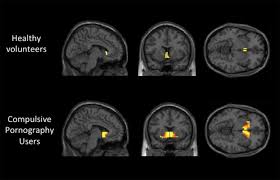

Your Brain On Porn -